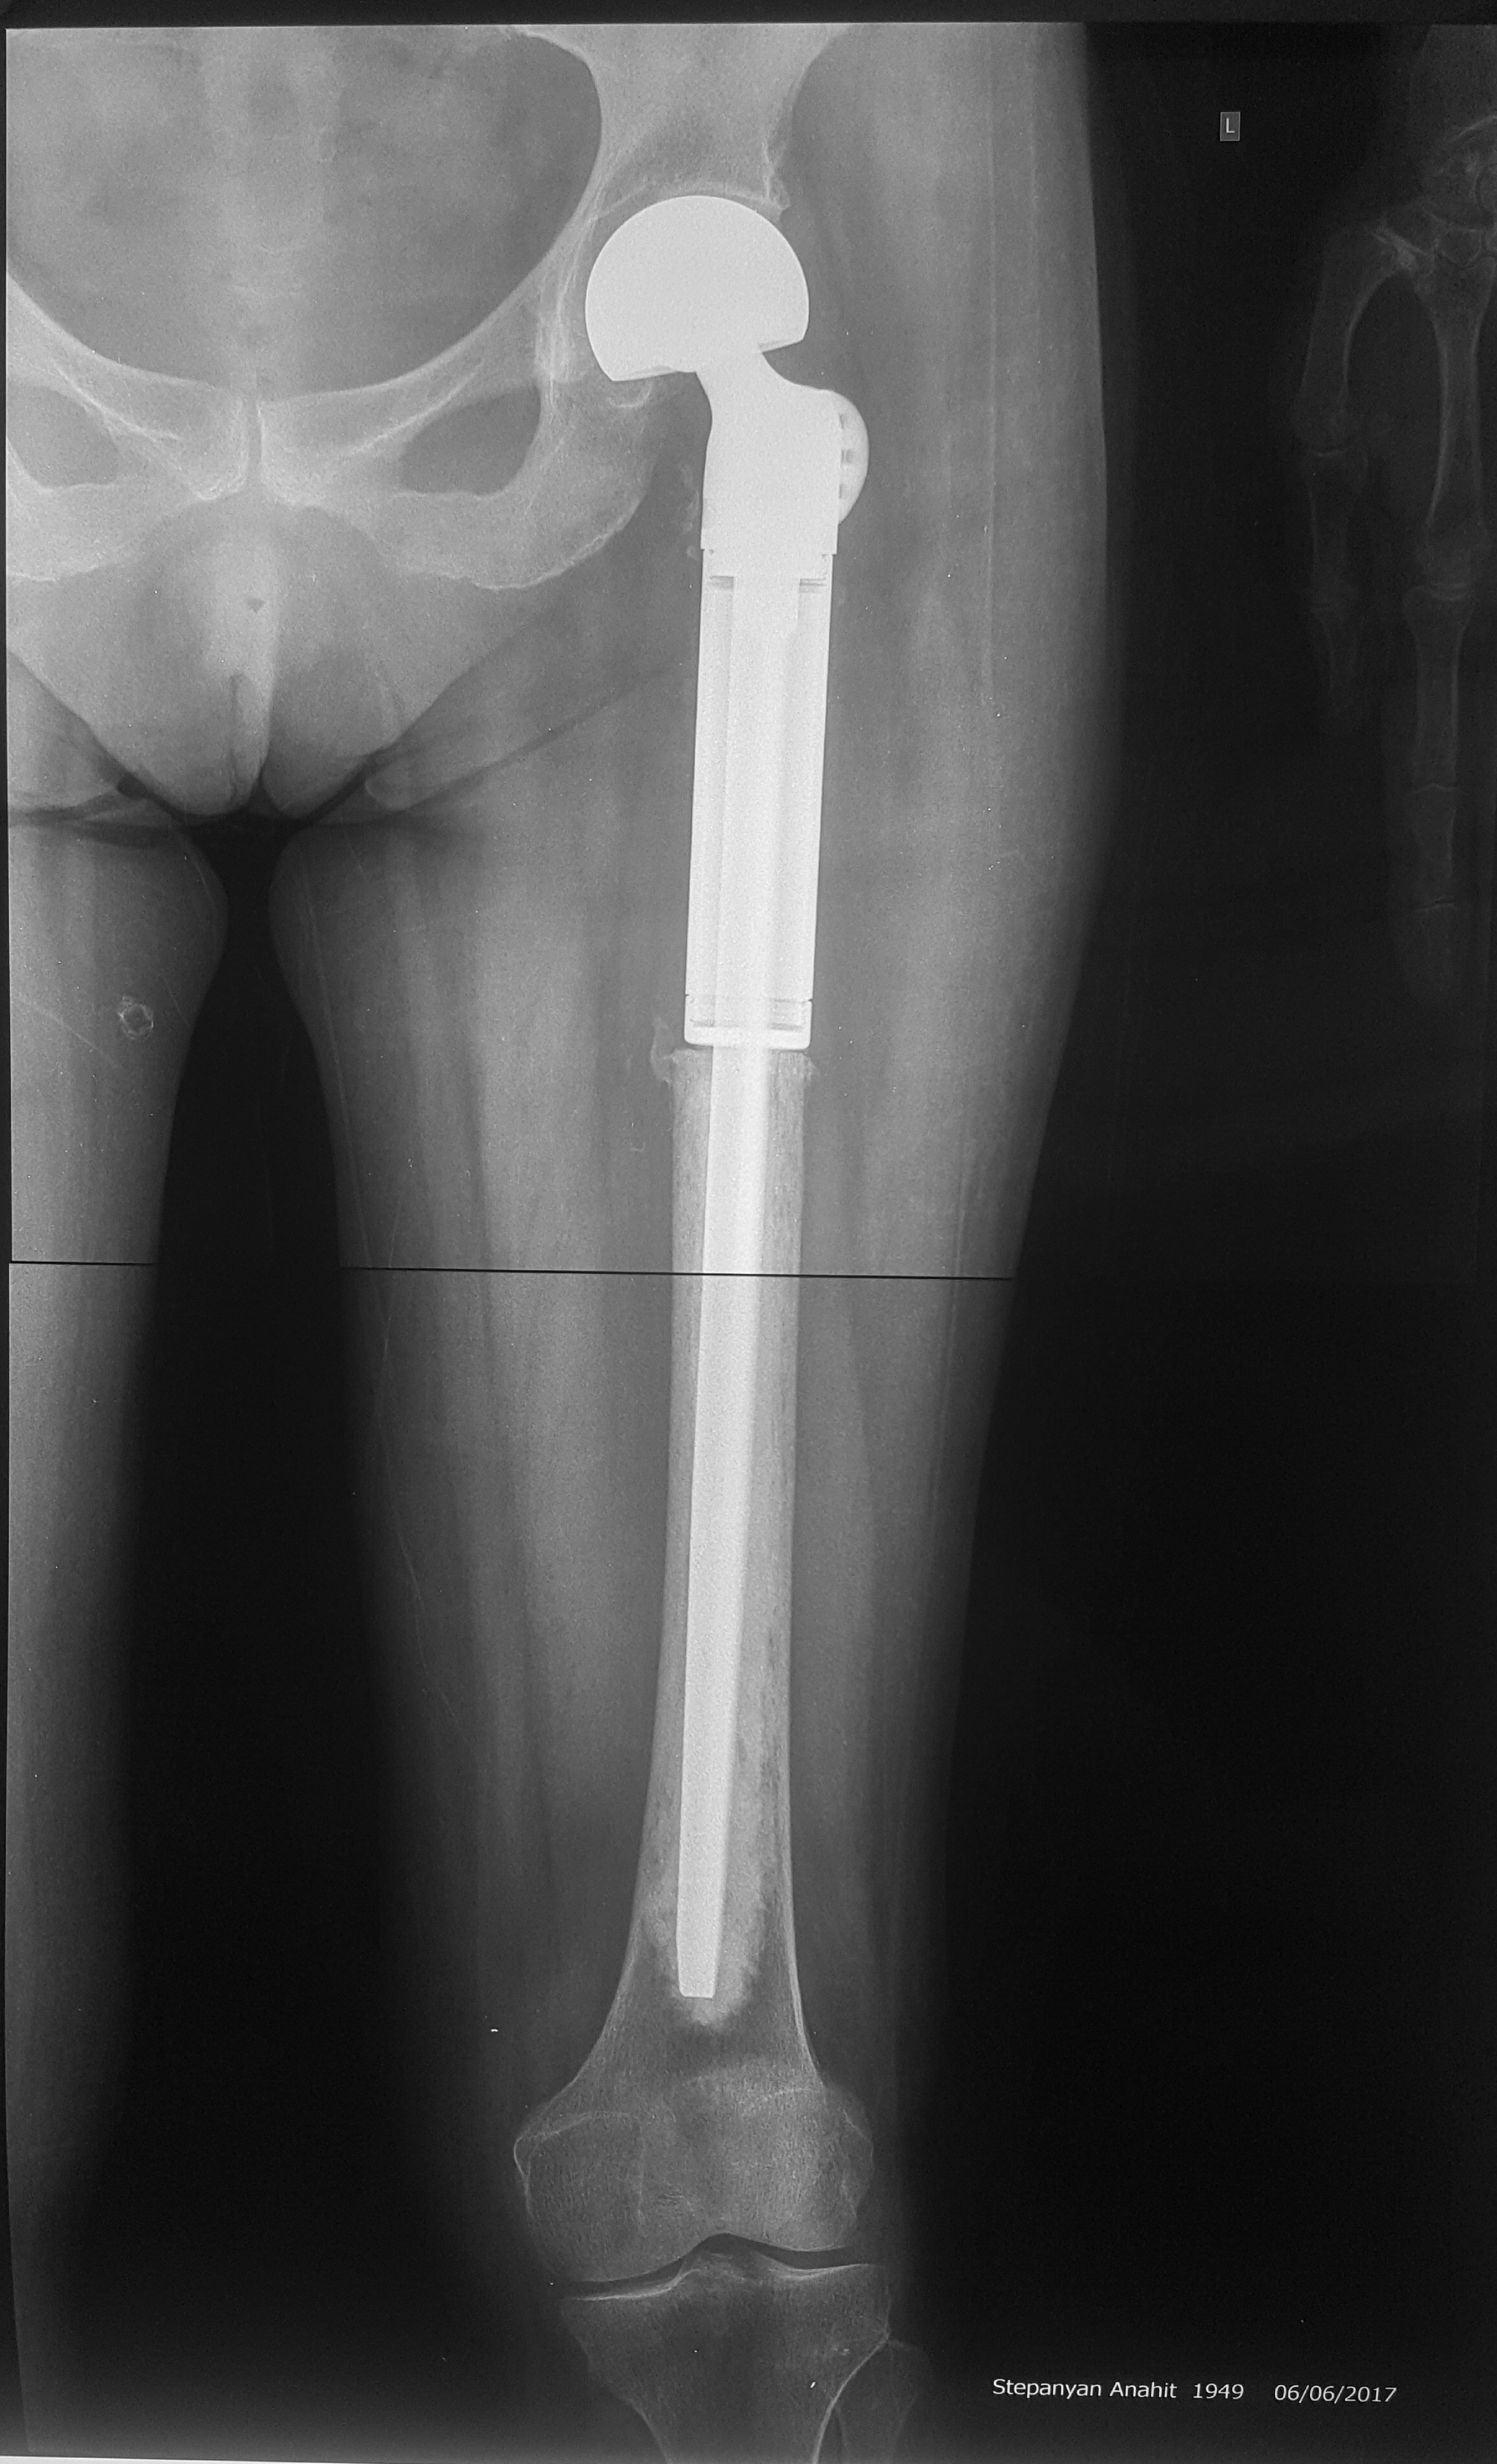

2. Остеосаркома большеберцовой кости

17-летний юноша обратился в МЦ ''Наири'' с жалобами на боли в области коленного сустава. После прохождения обследования у пациента была диагностирована остеосаркома большеберцовой кости.

После получения предоперационной химиотерапии в МЦ ''Наири" была проведена органосохраняющая операции – сегментарная резекция верхней трети большеберцовой кости и коленного сустава, замещение образовавшегося костно-суставного дефекта индивидуальным, изготовленным на заказ эндопротезом. В послеоперационном периоде пациент продолжил показанную по протоколам химиотерапию. В настоящее время лечение завершено, признаков прогрессирования заболевания нет, оперированная конечность функционально пригодная, опороспособность полная.

До операции

После операции